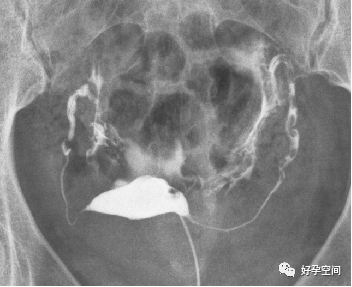

三、子宫输卵管造影通而不畅

1、轻度通而不畅

弥散相,延迟20分钟摄片,双侧输卵管内见较多造影剂残留影